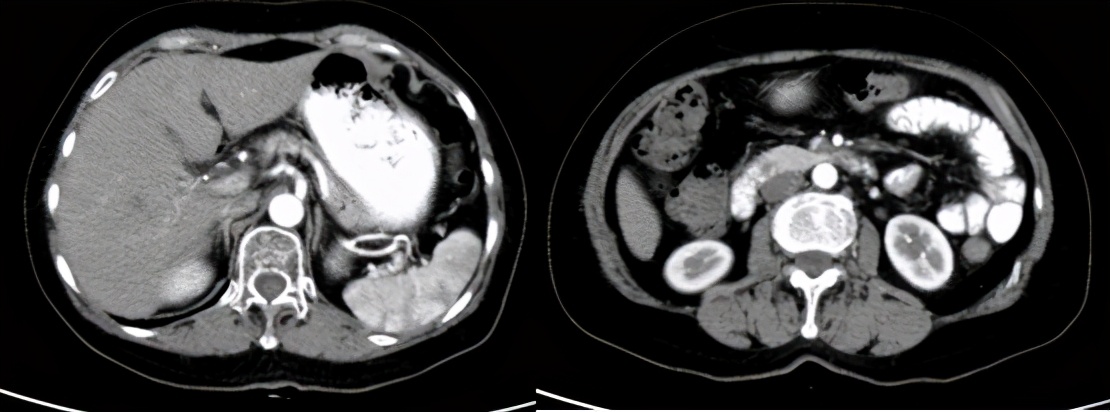

2020-04-14外院MR检查示:胰腺后上方不规则占位性病灶,腹膜后多发肿大淋巴结,考虑转移。(外院MR,未提供)

SBRT:胰体部病灶+腹膜后淋巴结病灶,剂量24GY/3F。

疗效评价:CR,截至2021.4,PFS为12个月,目前仍在随访中。

治疗后随访(2021.4)